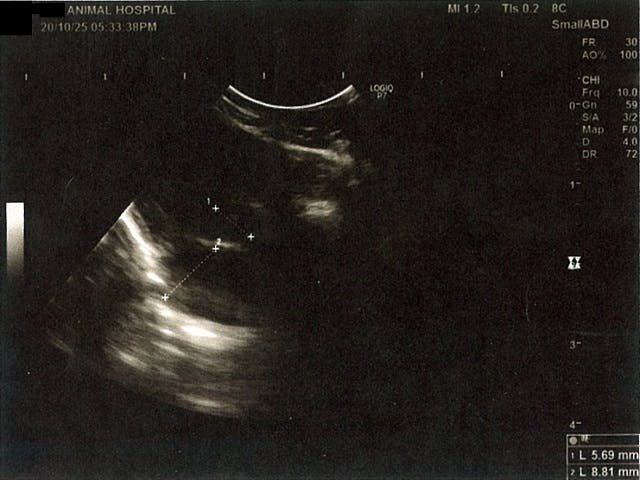

《心臓周りの胸部以外の全ての腹部で腹水がみられるとの診断です》

大網という部分で内臓を包む膜のようなものです。その周りに腹水が溜まっています。

右腎臓周りに腹水が確認できるエコー写真